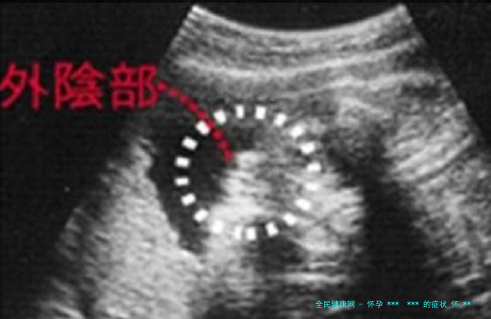

科学角度看 *** 判断

从医学角度, *** 最精准的判断方法是基因筛查和超声检查。孕期身体症状的变迁,更多体现了孕妇身体内激素水平、胎儿发育以及个体差距,而非助孕本身。比如晨吐的差别可能与孕激素水平凹凸相关,而非纯真由 *** 引起。